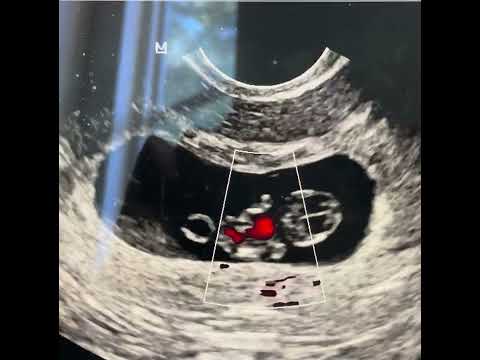

Since you could not be there with us, see below for the ultrasound. That is your baby Zee, our baby. We certainly did not mean to, but we made a life together that night.

I found out I was pregnant a week ago. It never occurred to me I could be pregnant. Nat and James figured it out. I thought I had a stomach virus. LOL At first, I was not happy about the news. That all changed when I went to see Dr. and Mr. Uareksit. and saw Little Strawberry. When I heard the baby's heartbeat I was in love.

Strawberry is the nickname I chose. I hope you like it.